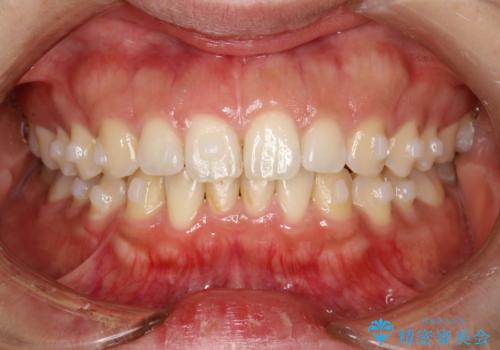

インビザライン中に歯の着色落としクリーニング PMTC

- インビザライン治療中に着色が気になるとのことでクリーニングを希望されました。PMTC30分コースを行いました。

インビザライン治療中には、歯の表面にアタッチメント(効率的に歯の移動をするもの)を設定します。そのため歯ブラシでは届きにくい細かい部分などに、歯石や着色がついてしまうことがあります。着色などを放置していると、着色なのか、虫歯なのかの判別もしずらく正確にお口の中の状態を診断できません。